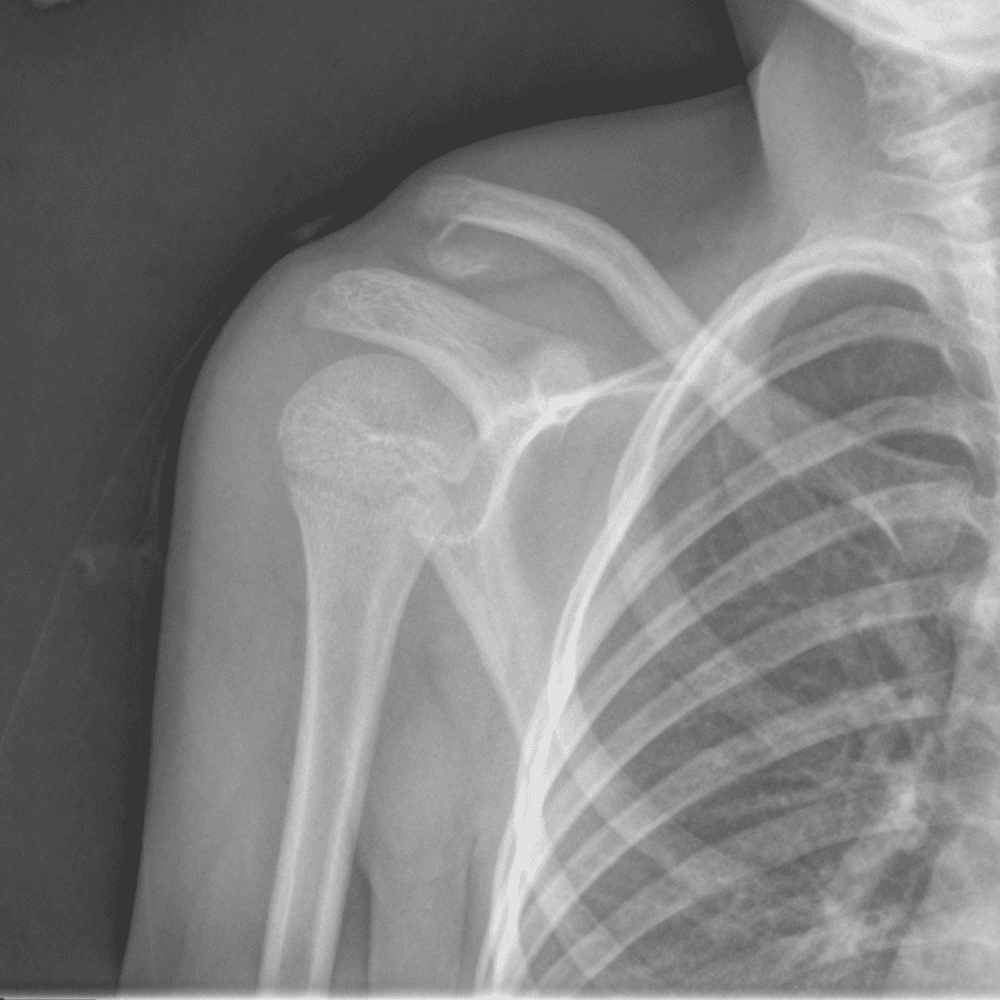

Simuliert den Dienst durch subtile oder schwierige Fälle und einige Normalbefunde.

30 Fälle